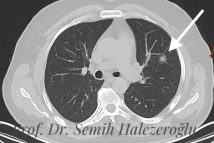

Prof. Dr. Semih Halezeroğlu